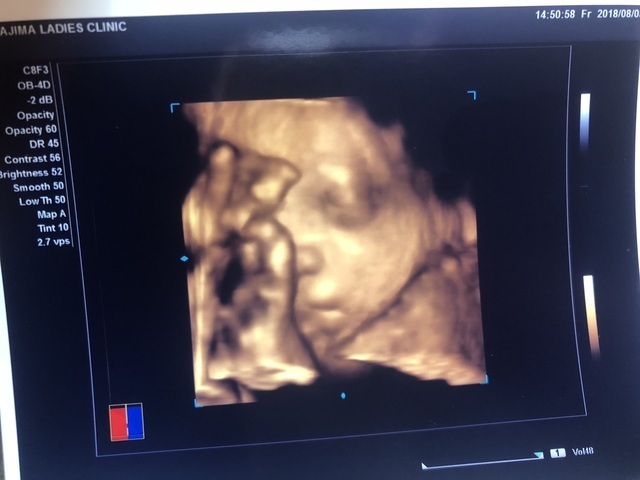

29週4日(29w4d・女の子)|yoco0318 さん(32歳)

エコー写真撮影時のエピソード:

切迫早産で入院していた時、詳しく心臓や顔を診る時に4Dで撮影しましょうと撮影して頂いた一枚です。

いつ陣痛がきてもおかしくないと言われましたが点滴と先生方、助産師さんのおかげで37週までお腹の中に居てくれました。

入院生活中に逆子になってしまったため、計画での帝王切開でしたが無事に産まれてきてくれて、生後1ヶ月を迎えました。

2ヶ月半の入院生活で私も主人もタフになり何が起きても動じなくなり、さらに自立して家事ができるようになりました。

入院生活は精神的にも落ち込み辛かったですが、今動ける事、娘と生活出来ることが何よりも幸せです。家事ができるようになってくれた主人には助けてもらっています。